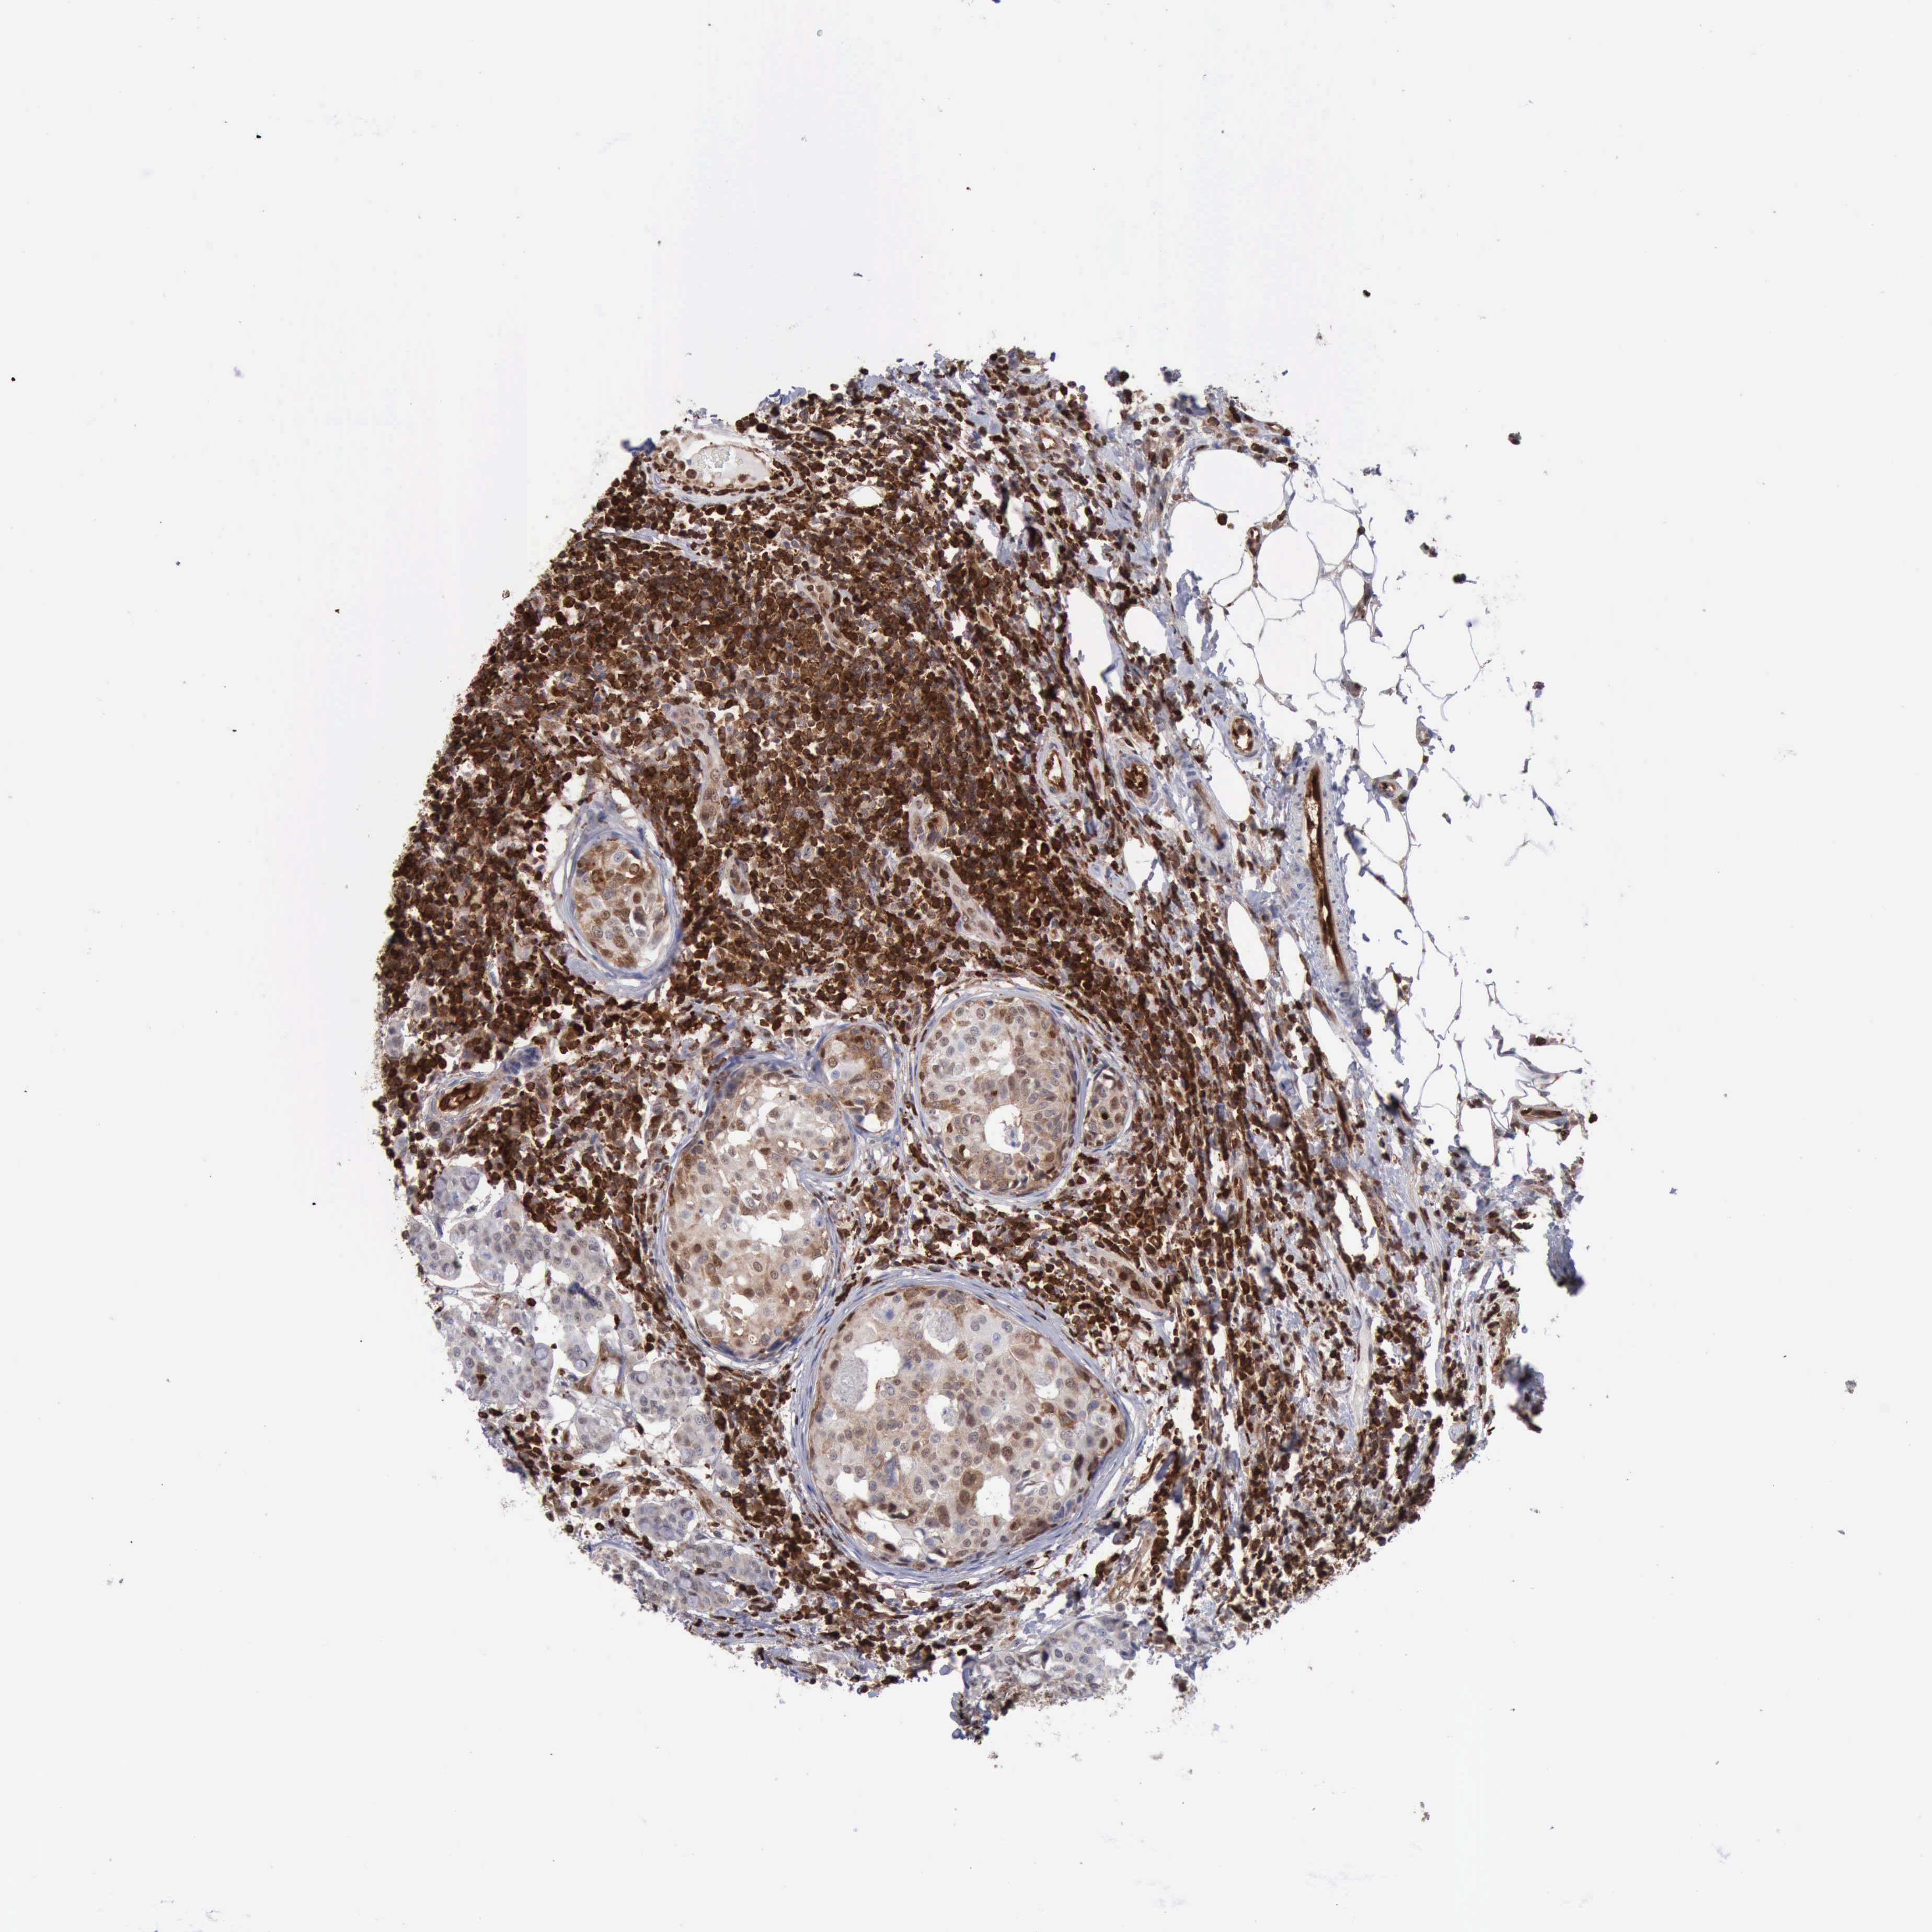

CANCER BREAST CANCER Show tissue menu

BRCA TCGA BRCA VALIDATION PROTEIN EXPRESSION